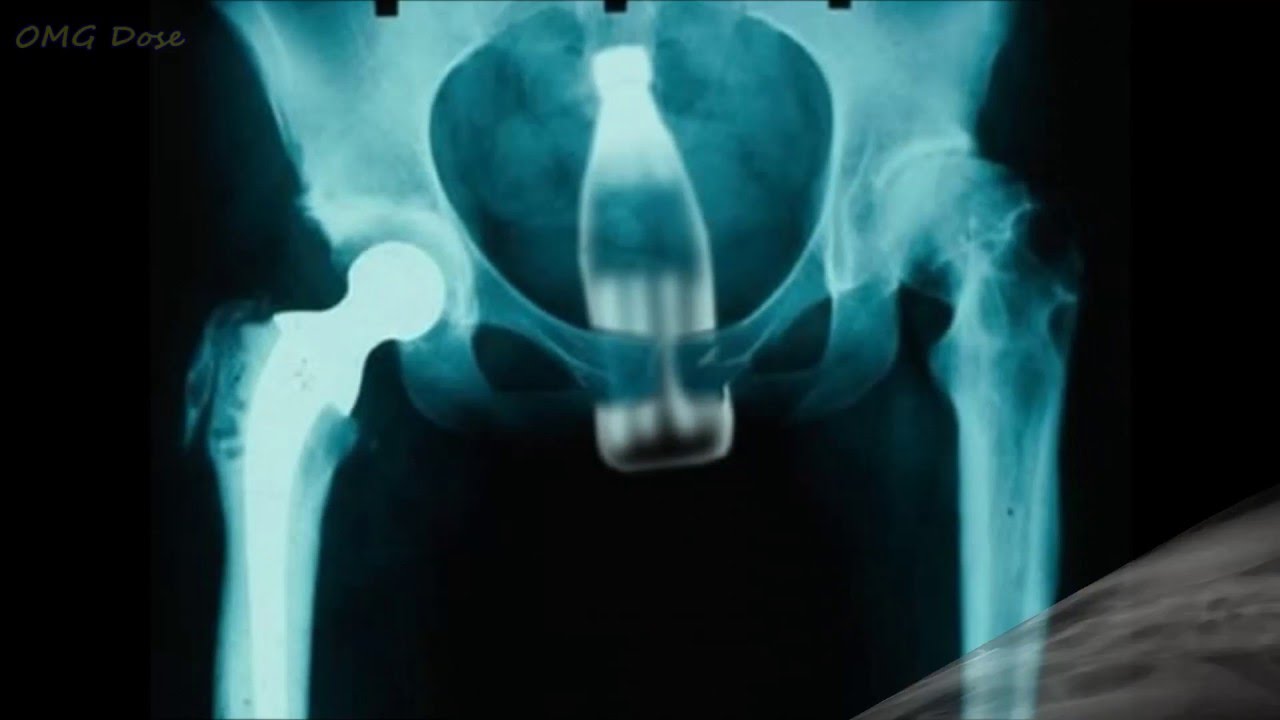

Strange object 01.jpg Strange object 02.jpg Strange object 03.jpg Strange object 07.jpg Strange object 10.jpg Подборка странных предметов, обнаруженных в человеческом теле. Пожалуй, элемент смешного присутствует ))) Хотя "носителям" вряд ли до смеха. )) Впрочем, кто им виноват?